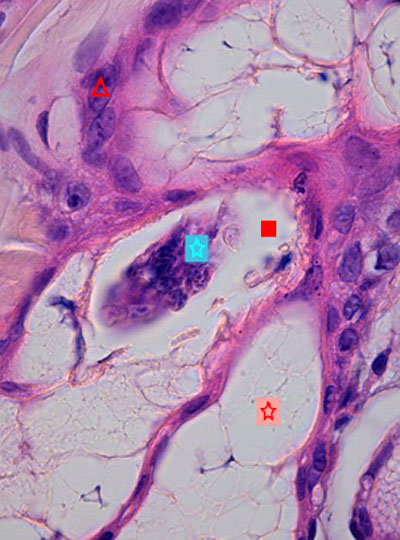

Photo 7 : (Hémalun-Eosine – X400) : Vue rapprochée d’un isthme folliculaire permettant

de visualiser une inflammation murale lymphocytaire et la lumière folliculaire contenant

trois silhouettes parasitaires démodéciques.

Légendes de la Photo 7 :

- Étoile turquoise = trois silhouettes parasitaires démodéciques dans la lumière folliculaire

- Carré rouge = tiges pilaires

- Étoile rouge = infiltrat inflammatoire lymphocytaire mural dans la paroi de la gaine épithéliale folliculaire externe et plasmocytaire au pourtour de l’isthme folliculaire

- Étoile rouge = lobules de glande sébacée hyperplasique

- Pointe de flèche rouge = gaine épithéliale folliculaire externe d’un follicule pileux